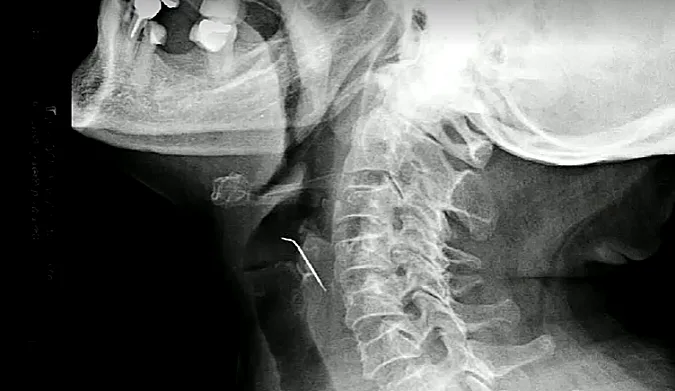

סיליה טלו, אישה בת 68 מפרו, אכלה גלדי שומן חזיר כשלפתע הרגישה משהו חד בתוך גרונה. מצבה התדרדר במהירות והיא החלה להקיא דם. היא הובהלה במהירות לבית החולים שם גילו הרופאים כי חתיכת ציפורן פצעה את אחד מעורקי הצוואר שלה והיוותה איום רציני על בריאותה.

הרופא שניתח אותה, ד"ר דייגל קויפל, תיר את ההליך העדין הנדרש להסרת ציפורן החזיר מגרונה. "היה סיכון של ניתוק קריש שעלול להגיע למוח", אמר.